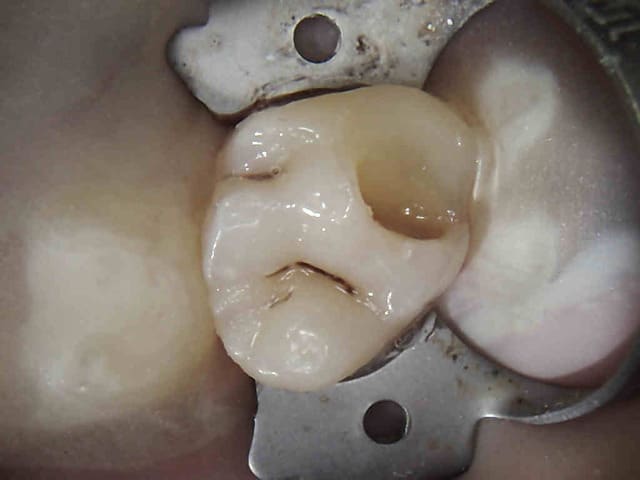

tient un boulot ou il y a un peu de tout.

bridge antérieur , car la pose d'implants nécessitait de la reconstruction trop importante, endo couronne sur les molaires mandibulaires par manque de hauteur, onlay. implants à la mandibule.

A noter les 2 PM maxillaires qui comportaient

chacune 3 canaux.